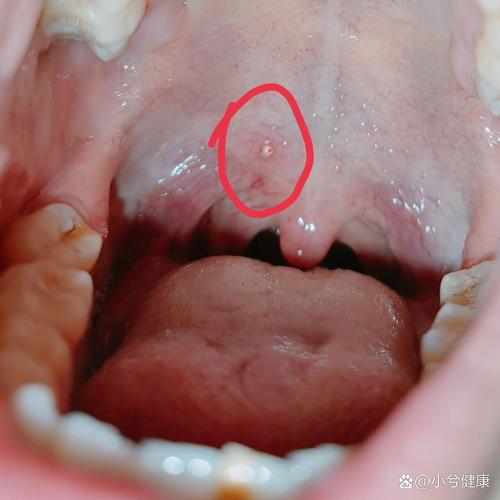

扁桃体或咽喉部的疣

- 和皮肤上的疣一样,HPV也可能在口腔黏膜上引起疣状增生。

- 外观:通常表现为单个或多个、粉红色或白色的、菜花状或乳头状的突起。

- 症状:通常没有明显疼痛,但如果疣体较大,可能会引起异物感、吞咽不适或口臭。